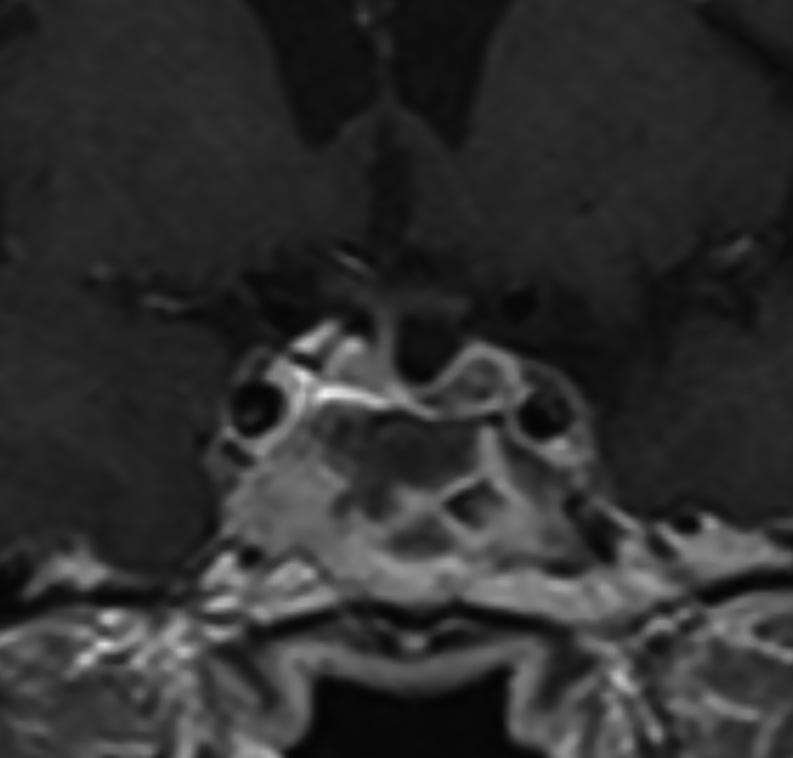

Gonadotropin-releasing hormone (GnRH) agonists, currently used in the treatment of advanced prostate cancer, have been described as a rare cause of pituitary apoplexy, a potentially life-threatening clinical condition. We report the case of a 69-year-old man with a known pituitary macroadenoma who was diagnosed with prostate cancer and started treatment with GnRH agonist leuprorelin (other hormones were not tested before treatment). Few minutes after drug administration, the patient presented with acute-onset severe headache, followed by left eye ptosis, diplopia and vomiting. Pituitary MRI revealed tumor enlargement and T1-hyperintense signal, compatible with recent bleeding sellar content. Laboratory endocrine workup was significant for low total testosterone. The patient was managed conservatively with high-dose steroids, and symptoms significantly improved. This case describes a rare phenomenon, pituitary apoplexy induced by GnRH agonist. We review the literature regarding this condition: the pathophysiological mechanism involved is not clearly established and several hypotheses have been proposed. Although uncommon, healthcare professionals and patients should be aware of this complication and recognize the signs, preventing a delay in diagnosis and treatment.

促性腺激素释放激素(GnRH)激动剂目前用于治疗晚期前列腺癌,已被描述为垂体卒中的罕见病因,垂体卒中是一种可能危及生命的临床病症。我们报告一例69岁男性病例,该患者已知患有垂体大腺瘤,被诊断为前列腺癌并开始使用GnRH激动剂亮丙瑞林进行治疗(治疗前未检测其他激素)。给药后几分钟,患者出现急性发作的严重头痛,随后出现左眼上睑下垂、复视和呕吐。垂体MRI显示肿瘤增大及T1高信号,符合鞍内近期出血表现。实验室内分泌检查显示总睾酮水平低。患者接受大剂量类固醇保守治疗,症状明显改善。本病例描述了一种罕见现象,即GnRH激动剂诱发的垂体卒中。我们回顾了关于这种病症的文献:其涉及的病理生理机制尚未明确确立,已提出几种假说。尽管不常见,但医护人员和患者应意识到这种并发症并识别其体征,以防止诊断和治疗延误。